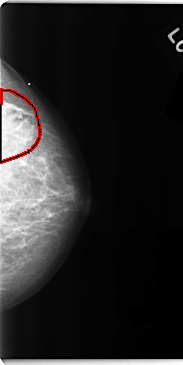

FILE: C_0113_1.LEFT_CC.OVERLAY

TOTAL_ABNORMALITIES 1

ABNORMALITY 1

LESION_TYPE MASS SHAPE IRREGULAR MARGINS ILL_DEFINED

ASSESSMENT 5

SUBTLETY 3

PATHOLOGY MALIGNANT

TOTAL_OUTLINES 1

BOUNDARY